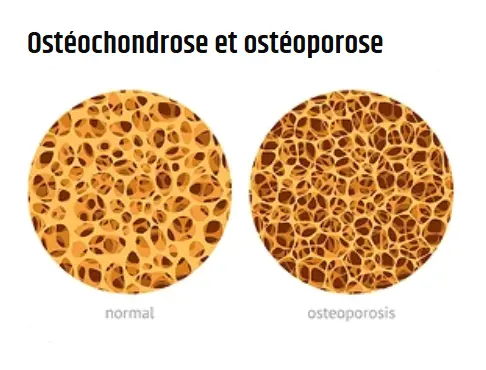

Quels sont les symptômes articulaires que Tromagel aide à combattre ?

Tromagel est un gel efficace et innovant pour les articulations. Il a été conçu en tenant compte de ce que l’organisme peut supporter. Il est naturel et vise à aider à réparer les articulations, à soulager la douleur et à réduire l’inflammation.

Qu'est-ce que Tromagel et comment agit-il ?

Tromagel est un gel naturel pour le soin des articulations qui pénètre profondément dans la peau pour réduire l’inflammation, soulager la douleur et restaurer la mobilité. Il améliore la circulation sanguine, favorise la régénération du cartilage et aide les articulations à retrouver leur liberté de mouvement.

Qui devrait utiliser Tromagel ?

Il est recommandé pour les personnes souffrant d’arthrite, d’arthrose, de douleurs dorsales ou aux genoux, de raideurs articulaires, de gonflements ou de mobilité réduite. Il convient également aux personnes qui passent de longues heures assises ou debout.

Le Tromagel peut-il guérir l'arthrite ou l'arthrose ?

Tromagel ne prétend pas guérir les maladies articulaires chroniques, mais il réduit efficacement la douleur, le gonflement et l’inflammation, aidant ainsi à restaurer la fonction articulaire naturelle et à améliorer la qualité de vie.